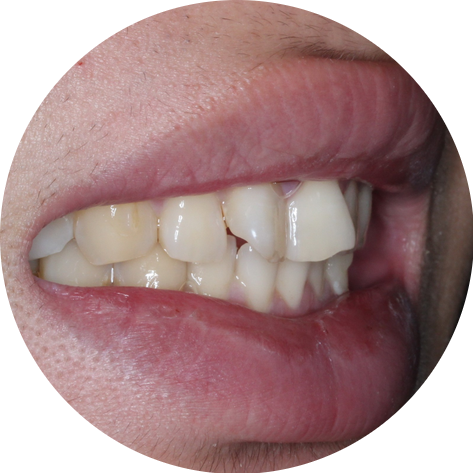

나비치아란?

앞니의 형태가 대칭적으로

뒤집혀 돌출된 치아를 말하며

앞니의 교합면이

V자 형태로 틀어진

상태를 말합니다.

나비치아교정! 15개월만에 빠른 교정 (교정 전)

투디치과(2D치과)

교정 전 사진을 보시면

앞니의 모양

특히 11, 12번 치아의 형태가

V자 모양으로 대칭적이게

틀어져 있는 모습입니다.

측면에서 보았을때 나비치아가

두드러져 보였던 교정 전과 달리

완만한 곡선의 형태로 앞니가 배열된

교정 후 모습입니다.